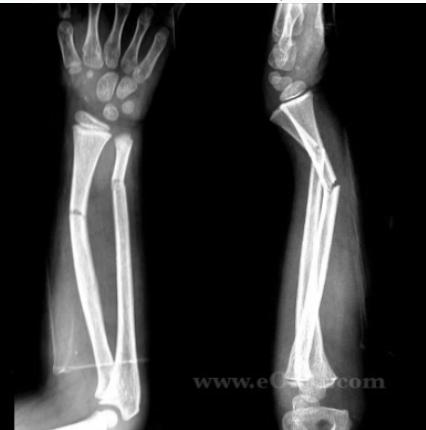

- Anatomical reduction is a must to preserve function

- Nondisplaced: Closed reduction, casting, close regular follow-ups

- Unstable or re-displace in cast: Closed reduction, elastic nail